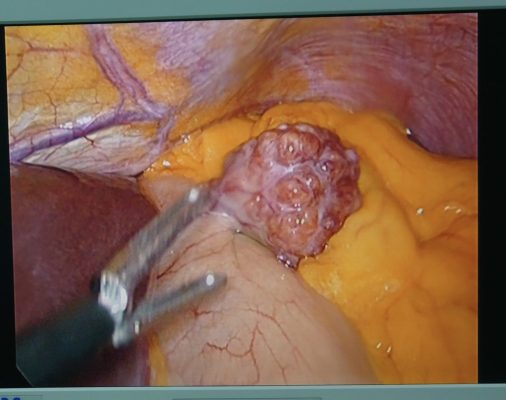

– Bệnh nhân được chẩn đoán Theo dõi GIST thân vị dạ dày/ Thiếu máu mạn tính mức độ trung bình và được điều trị phẫu thuật nội soi cắt dạ dày hình chêm bằng dao siêu âm, lấy u làm giải phẫu bệnh lý, trước và trong mổ được truyền 02 đơn vị hồng cầu khối nhóm máu [O+]. Sau mổ bệnh nhân ổn định, xét nghiệm máu sau mổ: Hồng cầu 5,63 T/l; Hb 110 g/l; HCT 36,9%. Bệnh nhân được xuất viện sau 05 ngày điều trị.

U sợi đơn độc dạ dày của bệnh nhân của chúng tôi đã được điều trị bằng phẫu thuật cắt phần dạ dày chứa khối u hình chêm. Phẫu thuật cắt bỏ dạ dày hình chêm được thực hiện ở 4 trong số 6 trường hợp, trong đó có 1 trường hợp sử dụng dao siêu âm giống như phương pháp của chúng tôi.5-10 Các bệnh nhân cho thấy tiến triển tốt rõ rệt về lâm sàng sau phẫu thuật và không tái phát khi theo dõi, ngay cả khi không có bất kỳ liệu pháp điều trị hậu phẫu cụ thể nào. Ở bệnh nhân của chúng tôi, phẫu thuật cắt dạ dày hình chêm bằng dao siêu âm đã được sử dụng để cắt bỏ tổn thương u sợi đơn độc. Dựa trên tìm hiểu của chúng tôi, trường hợp của chúng tôi là trường hợp thứ hai được báo cáo về điều trị u sợi đơn độc dạ dày bằng phương pháp phẫu thuật nội soi cắt dạ dày hình chêm bằng dao siêu âm. Trường hợp đầu tiên được báo cáo ở Nhật Bản năm 2015, bệnh nhân hồi phục tốt sau phẫu thuật và không ghi nhận tái phát sau 8 tháng theo dõi.8 Do đó, phẫu thuật nội soi cắt dạ dày hình chêm nên được khuyến cáo ở những bệnh nhân u sợi đơn độc dạ dày để đảm bảo loại bỏ hoàn toàn tổn thương, hạn chế tái phát và di căn cũng như đảm bảo hồi phục sau mổ tốt hơn cho bệnh nhân.